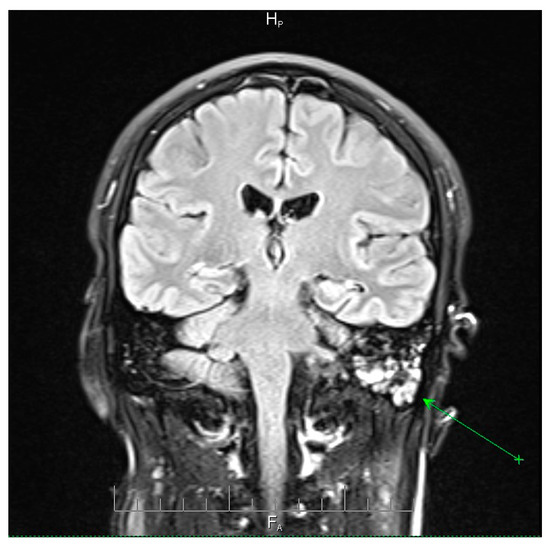

Neuroimaging revealed mild ethmoidal/sphenoidal sinus opacification and left mastoid air cell involvement without evidence of parenchymal lesions or venous sinus thrombosis (Figure 1, Figure 2 and Figure 3). Coronal and axial T2-weighted MRI sequences revealed para-fluid collections within the left mastoid air cells extending toward Citelli’s angle (Figure 1, Figure 2 and Figure 3), consistent with an otogenic focus and a possible contiguous route for intracranial spread.

Figure 2.

Axial T2-weighted MRI scan demonstrating opacification of the left mastoid air cells with a hyperintense signal (green arrow), indicative of mastoid involvement. This finding suggests a potential contiguous source of intracranial infection in this patient. No acute lesions, hemorrhage, or signal abnormalities were observed in the cerebellum or brainstem, and the surrounding brain parenchyma appeared normal. These imaging features support localized mastoid pathology without evidence of intracranial extension, providing important radiological context for the patient’s clinical presentation and aiding in the assessment of the infection risk. AH = anterior-head. PF = posterior- foot.